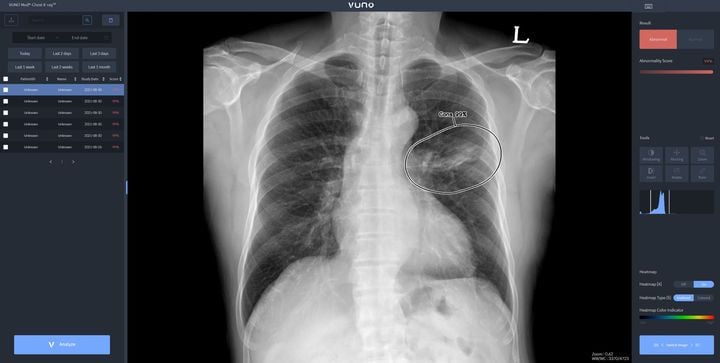

뷰노 메드 체스트 엑스레이는 흉부 엑스레이 영상에서 주요 5개 소견을 자동 판독, 폐암·결핵·폐렴 등 중증 질환 사전 감별을 지원한다. 의료진이 의심 환자 추려내기에 드는 시간을 단축하고 판독 정확도를 높이는 역할이다. 특히 이번 기술은 기존 판독의 한계였던 의료진의 피로누적, 주관적 해석 문제를 극복했다.